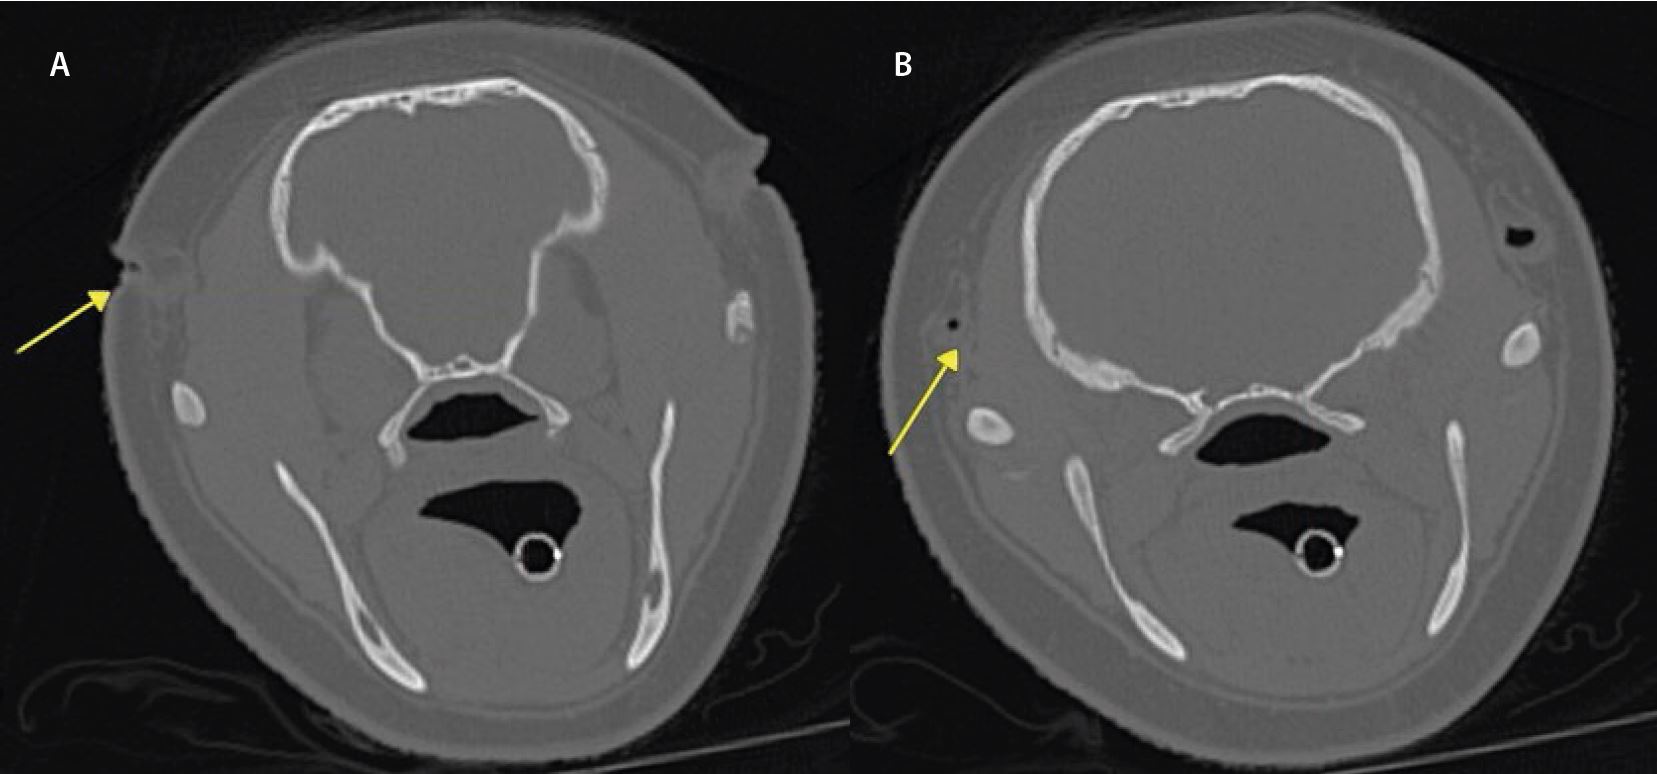

На малюнках 1a і 1b показано слуховий прохід пацієнта в кістковому фільтрі (жовті стрілки).

На аксіальних зображеннях видно вузький слуховий прохід (а), виражене звуження лівого зовнішнього слухового проходу (б), набряк м’яких тканин лівого зовнішнього слухового проходу на постконтрастному скануванні та набряк м’яких тканин у лівій барабанній порожнині. Звужений зовнішній слуховий прохід з потовщеною і неправильною стінкою сумісний з інфекцією зовнішнього вуха. Ослаблення м’яких тканин лівої порожнини вказує на середній отит (запалення середнього вуха).

Малюнок 1c і 1d. На малюнку 1c показано заблокований слуховий прохід у фільтрі м’яких тканин, а на малюнку 1d показано заповнену рідиною порожнину в кістковому фільтрі.